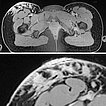

In der koronaren T2-gewichteten, fettunterdrückten MRT auf Höhe des proximalen Oberschenkels ist die lymphatische Malformation aufgrund der enthaltenen interstitiellen Flüssigkeit (Lymphe) stark hyperintens und netzartig verteilt.

Gleiche MRT-Schicht in der nativen T1-Wichtung zeigt die LM hypointens im hyperintensen subkutanen Fettgewebe, entsprechend der enthaltenen Lymphflüssigkeit.

In der axialen fettunterdrückten T1-Wichtung nach KM-Gabe (oben Übersicht, unten Ausschnitt) findet sich die stärkste Anreicherung in den kutan gelegenen, expophytischen, mikrozystischen Anteilen in der Haut. Die darunter liegende LM im subkutanen Fettgewebe reichert dagegen kaum an.

In der entsprechenden Computertomographie ist die LM mit ihrer Flüssigkeitseinlagerung und bindegewebigen Komponente etwas hyperdenser als das umgebende subkutane Fettgewebe dargestellt, der Weichteilkontrast ist schlechter als in der MRT. Es findet sich in der CT auch keine KM-Anreicherung. Beachte in der Ausschnittsvergrößerung (unteres Bild) die Verdickung der Haut durch die kutanen mikrozystischen Anteile der LM.